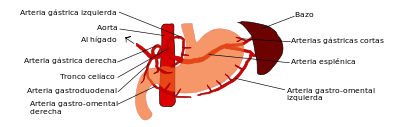

1º- Tronco celiaco: vasculariza desde el esófago distal hasta la 2ª porción duodenal o duodeno descendente. Se compone de:

- Arteria gástrica izquierda.

- Arteria hepática común (se divide luego en gastroduodenal y hepática propia).

- Arteria esplénica.

2º- Arteria mesentérica superior (AMS): desde 3ª porcion duodenal hasta el colon transverso y flexura esplénica. Mencionar que la arteria gastroduodenal (primera rama de la hepática común) forma una importante conexión con la AMS.